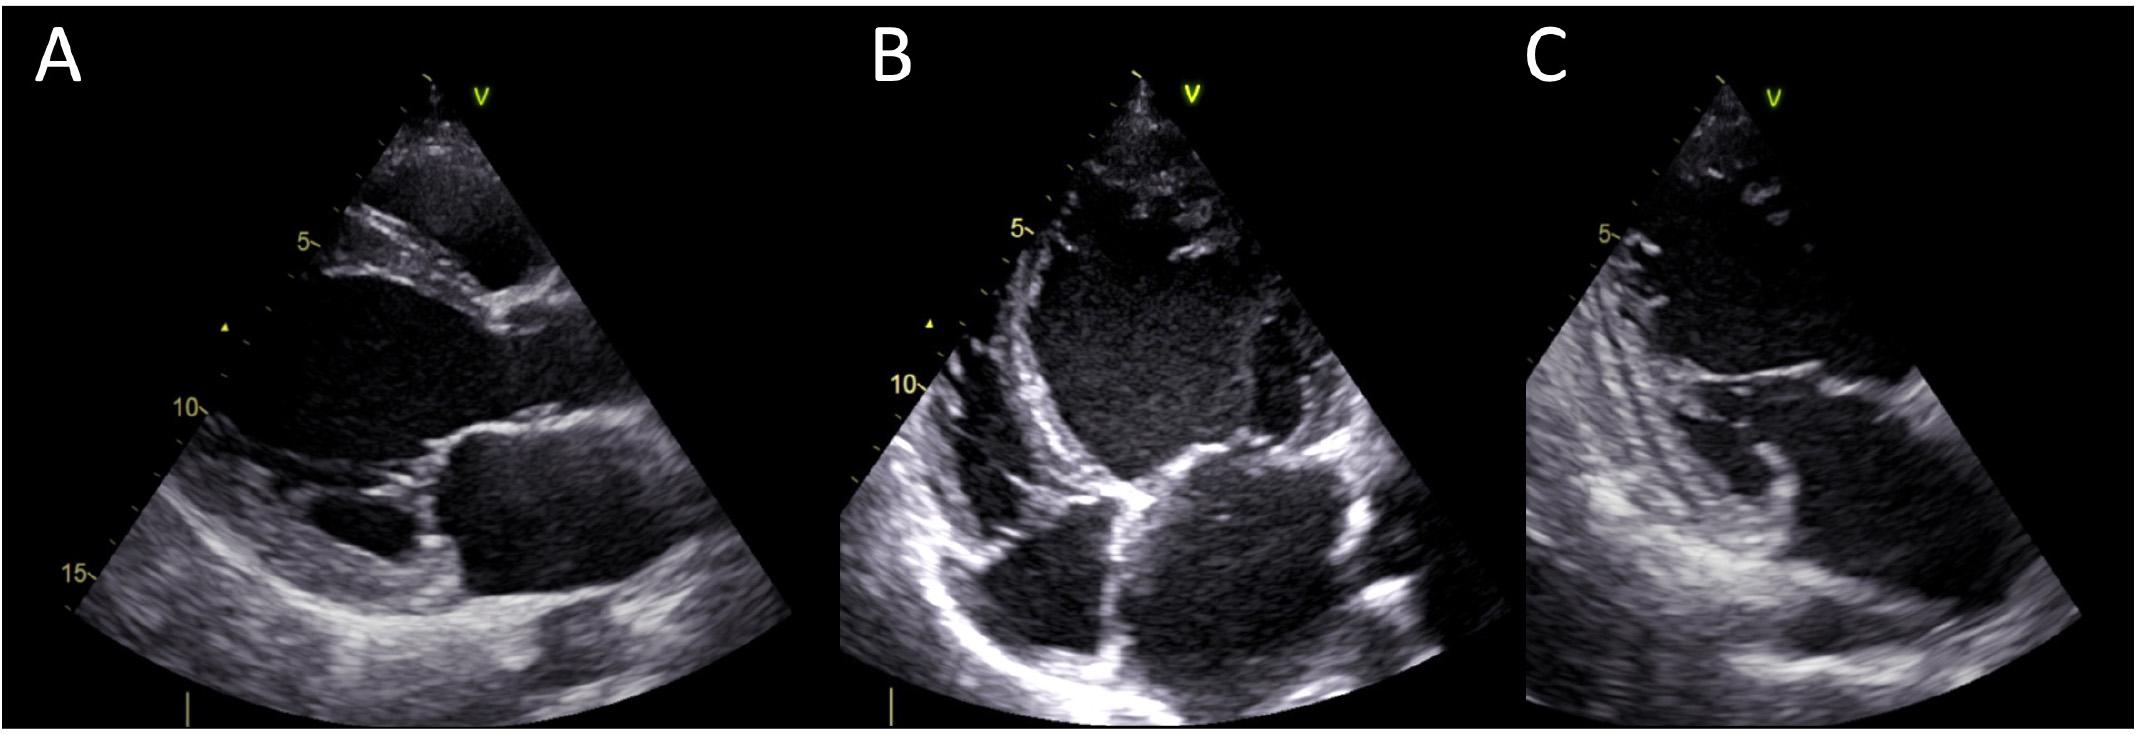

Figure 2